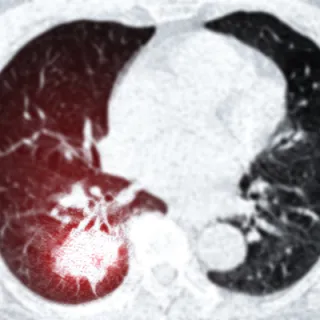

It is extremely important for the ordering clinician to understand the difference between a low-dose CT (LDCT) chest, a routine (diagnostic) CT chest, and a High Resolution CT Chest. We frequently enc... ...more

Imaging

September 02, 2025•2 min read

The Fleischner Criteria, provides standardized recommendations for the management of incidentally detected pulmonary nodules on CT scans. The key word here is incidentally detected, this is not to be... ...more

Imaging ,Cancer

September 01, 2025•1 min read